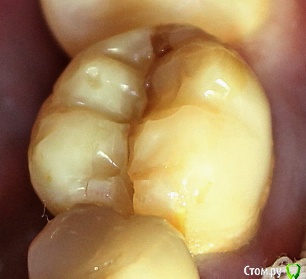

ARislanV Опубликовано 28 мая, 2015 Поделиться Опубликовано 28 мая, 2015 Приветствую всех, Здравствуйте, Начинаем!Пол года назад лечил 36Pt зуб, коронковая часть разрушена на 70 %, восстановил все композитом с перекрытием бугров.Сейчас зуб треснул, по словам удалявшего хирурга трещина до бифуркации. Почему он раскололся? Ведь что интересно, трещина прошла не по краю зуб/пломба ( в самом слабом месте), а посередине пломбы т.е. пломба разорвалась по палам. А какая сила должна была быть, что бы разорвать пломбу по полам?) И следующий вопрос, что делать и как делать, чтобы такого не было? ( потому что мне было очень не приятно видеть такое со своей работой) Ссылка на комментарий

ARislanV Опубликовано 28 мая, 2015 Автор Поделиться Опубликовано 28 мая, 2015 Я такие зубы когда пац не хочет протезироват, делаю запис в карте что рекомендовано тота тота с последствиями ознакомлен и т.п. Половина зуба заливаю жидким композитом а потом пакуемым вост сверху но стенки зуба укоротив по высоте и это укорочение компенсирую пакуемым. Типа как внутри полости пломба с переходом на края стенок. Пломба ввиде грибка. Палюбому ел кашу))Мой зуб был восстановлен именно таким способом, как вы описываете( в виде гриба)Но какова должна была быть сила, что бы разорвать пломбу пополам? Ссылка на комментарий

Brigita Опубликовано 31 мая, 2015 Поделиться Опубликовано 31 мая, 2015 (изменено) Мой зуб был восстановлен именно таким способом, как вы описываете( в виде гриба)Но какова должна была быть сила, что бы разорвать пломбу пополам?http://s019.radikal.ru/i635/1505/8f/9418a177913ft.jpg Изменено 31 мая, 2015 пользователем Brigita 1 Ссылка на комментарий